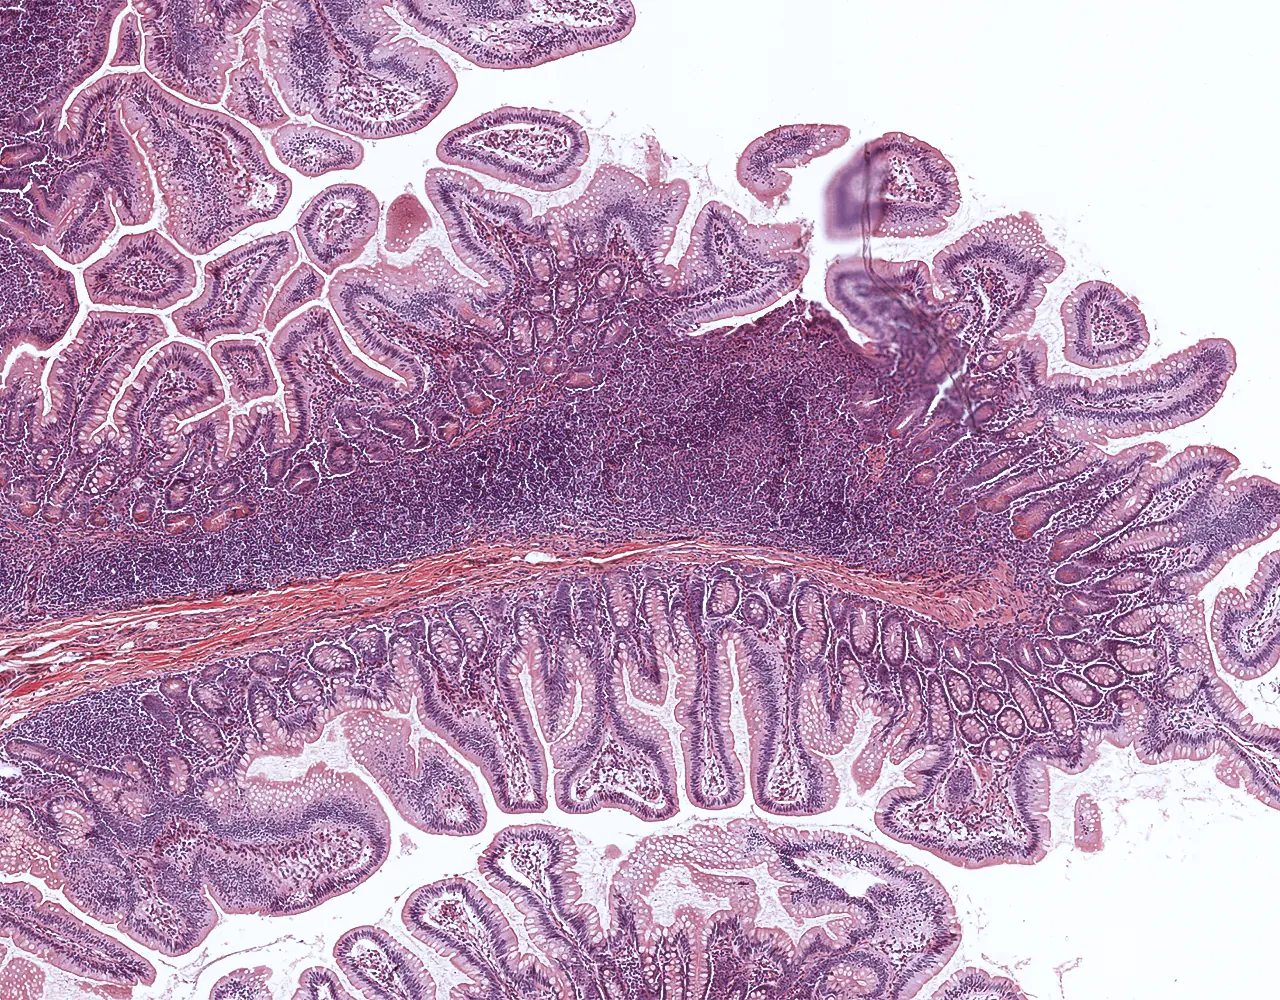

- Contribution to immune defence through gut-associated lymphoid tissue, especially Peyer patches in the ileum.

- Microscopically, the wall is composed of 4 layers from the inside outward: mucosa, submucosa, muscularis propria, and serosa.